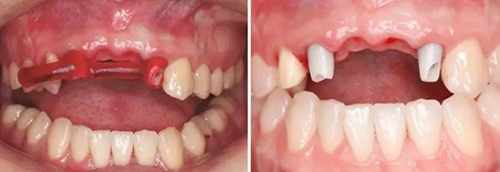

圖1 植骨術(shù)前口內(nèi)正面觀 圖2 植骨術(shù)前口內(nèi)頜面觀

患者,女性,23歲,大學(xué)生?;颊哂?年前因外傷導(dǎo)致上前牙缺失,期間行可摘局部義齒修復(fù),自覺每天摘帶不便,且影響正常發(fā)音及美觀,至我科要求種植修復(fù)。平素體健,無全身系統(tǒng)性疾病,無特殊藥物服用史,無藥物、材料等過敏史,無吸煙、夜磨牙等不良習(xí)慣??谕鈾z查見口腔頜面部對(duì)稱,張口度正常,中位唇線,中位笑線??趦?nèi)檢查見12、11、21、22缺失,缺牙區(qū)牙槽嵴薄。覆牙合覆蓋淺,23反牙合??谇恍l(wèi)生狀況良好。拍攝CBCT示:12位點(diǎn)可用牙槽骨高度為16.4mm,寬度為3.6mm;22位點(diǎn)可用牙槽骨高度為19.5mm,寬度為3.2mm。

臨床診斷:上頜牙列缺損(12、11、21、22缺失)